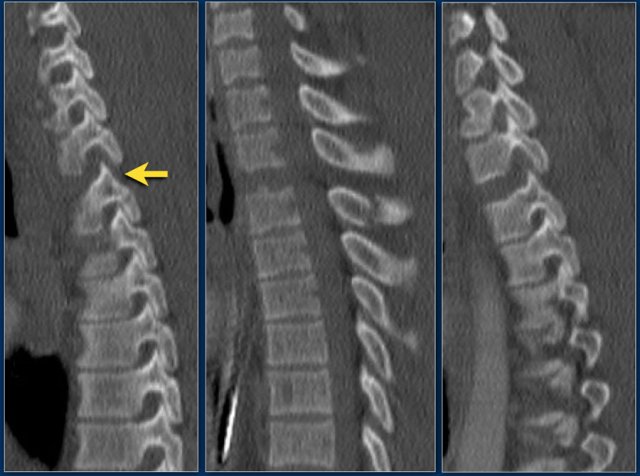

Case 6

Look at the images.

How would you describe the morphology and the PLC?

Then scroll to the next images.

The findings are:

1. Morphology: Distraction - 4 points

2. PLC: always torn in posterior distraction - 3 points

3. TLICS based on imaging: 7 points

The key point in this case is that you should not describe this morphology as burst - 2 points.

The horizontal fractures on the posterior side and the increased interspinous distance indicate distraction, which means a higher score for morphology.

Always go for the highest possible score in TLICS.